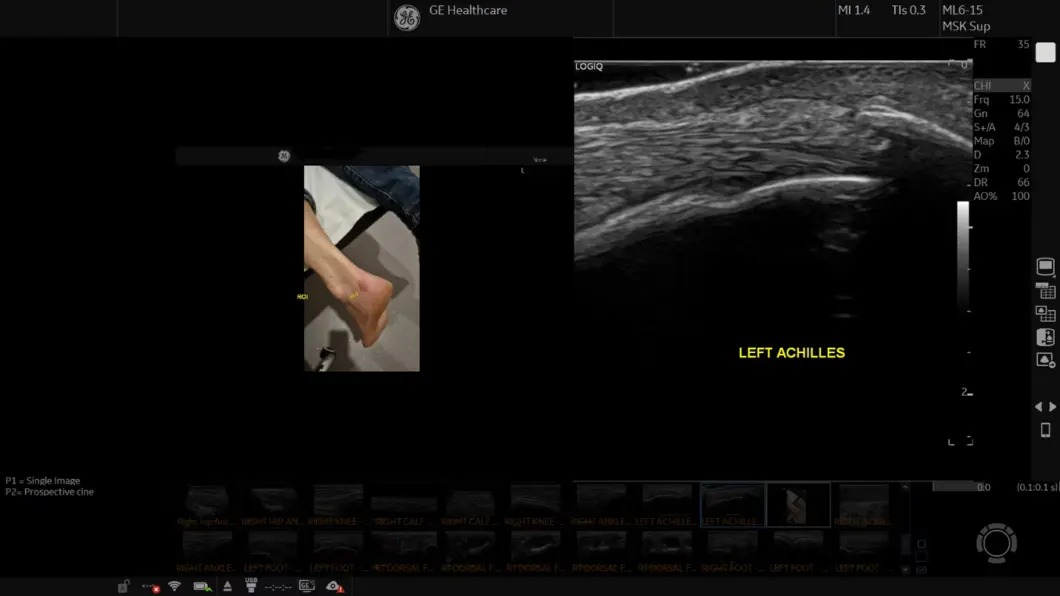

LOGIQ Fortis je moderno ultrazvučno rješenje, opremljeno snažnim alatima za provođenje cijelog spektra pretraga i postupaka, prilagodljivo svakoj potrebi i iznimno jednostavno za korištenje. Zahvaljujući svom pametnom i tankom dizajnu, uređaj se može brzo i jednostavno transportirati i uvijek je tamo gdje vam treba. Nagrada iF Design Award, jedno od najprestižnijih dizajnerskih natjecanja na svijetu, odaje počast izvanrednom dizajnu od 1953. godine.

LOGIQ Fortis je vaše ultrazvučno rješenje za svakog pacijenta – od glave do pete, od pretile do mršave osobe, od novorođenčadi do gerijatrijske dobi, za sve u vašoj ustanovi. Skenirajte pomoću baterijskog napajanja za provođenje ispita bilo gdje.

Opremljen tehnologijom snimanja sljedeće generacije, LOGIQ Fortis je vaše pristupačno sveobuhvatno ultrazvučno rješenje za snimanje cijelog tijela.

Naša moćna cSound™ arhitektura povećava snagu obrade i protok podataka kombiniranjem XDclear™ sondi i cSound Imageformer-a s naprednom tehnologijom Speckle Reduction Imaging (SRI). Rezultat je iznimna kvaliteta slike, jasnoća i klinička pouzdanost u širokom rasponu kliničkih primjena.